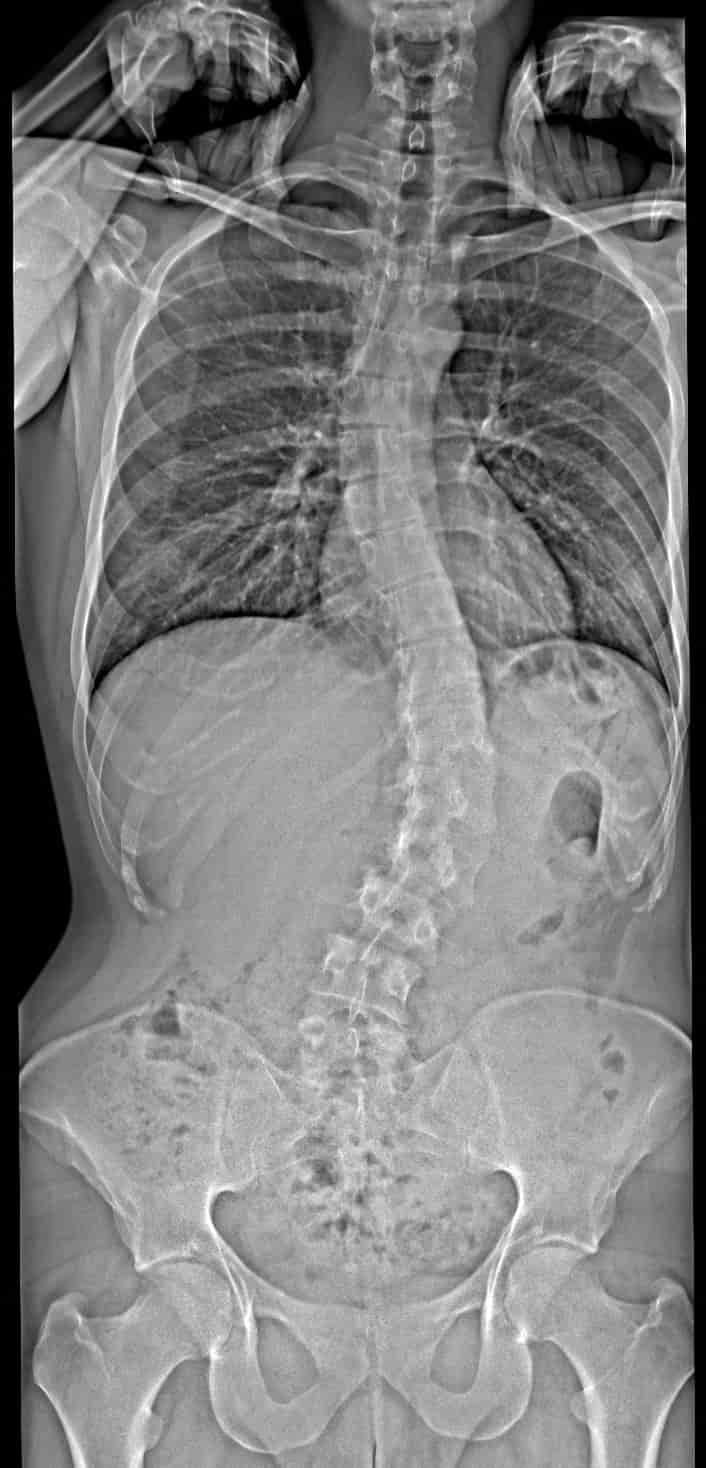

Zusätzlich wurde ein Röntgenbild der Wirbelsäule angefertigt. Ergebnis: eine schwere Skoliose, die bisher unentdeckt geblieben war. Der Radiologe hat einen Cobb-Winkel oben von 30° und unten von 45° festgestellt.

- Dateianhänge

- Bild 09.09.25 um 11.01-min.jpeg

- Meine Wirbelsäule

Zu Deinen Schmerzen ist noch zu sagen, dass Du eine asymmetrische Skoliose mit ganz unterschiedlich hohen Gradzahlen hast. Eine solche Skoliose ist laut einer Studie beschwerdeanfälliger als eine symmetrische Skoliose mit gleichen oder ähnlichen Winkeln.

Das wurde gemacht, ich habe das Bild angehängt. Beim Orthopäden wurde dazu allerdings überhaupt nichts gesagt. Kannst du etwas auf dem Bild erkennen, das für mich relevant sein könnte? Ich habe da leider überhaupt keine Expertise.Eine Frage, die ich allen männlichen Usern mit Fehlstellungen stelle: Hast du evtl. auch einen Rundrücken (Hyperkyphose) oder ein Hohlkreuz (Hyperlordose)? Das sieht man in einem seitlich aufgenommenen Röntgenbild, das leider oft in der Diagnostik fehlt.

Also eine Hyperkyphose/Hyperlordose hast Du wohl nicht, es sieht eher so aus, als ob die natürliche BWS Kyphose etwas abgeschwächt ist.Kannst du etwas auf dem Bild erkennen, das für mich relevant sein könnte?